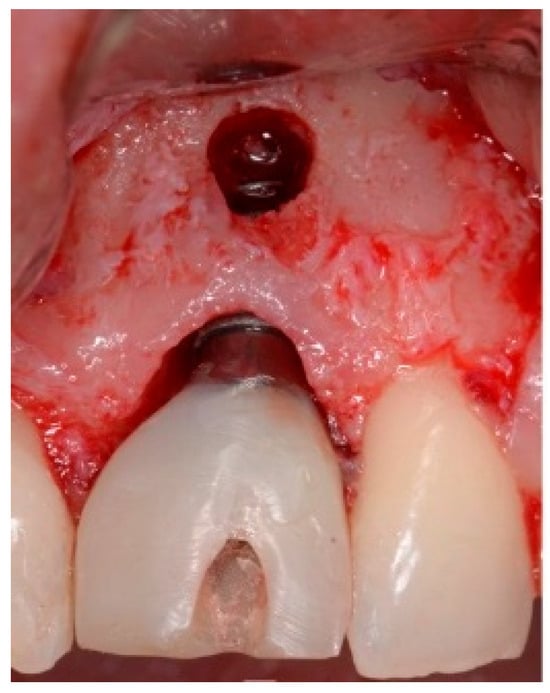

A 50-year-old female in good health and a non-smoker presented to our clinic with a failing maxillary left central incisor (Figure 13). The treatment plan consisted of the extraction of the existing tooth and replacing it with an implant. The preoperative surgical protocol described in patient 1 was followed. An L-shaped aesthetic flap design was used, revealing a buccal wall defect (Figure 14). The implant was placed with a screw-retained chair-side temporary crown (Figure 15), followed by the placement of bone graft material over the boney defect (Figure 16). A double-layer collagen membrane was placed and the flap closed. After six months, the final ceramic crown was inserted (Figure 17).

Figure 13.

Clinical view of extraction site (note tissue above tooth #9).

Figure 14.

Clinical view of extraction site implant.

Figure 15.

Clinical temporary crown.